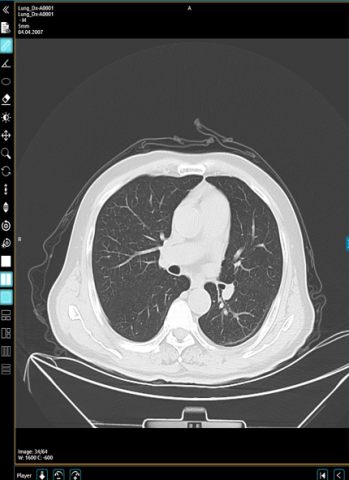

CT scans can show a tumor's shape, size, and location. CT images are now widely used as a screening tool for detecting and diagnosing a variety of tumors. It has also become an important component of any comprehensive medical examination. The CT images provide extensive information about lungs. The input image is as shown in Figure 6.

After pre-processing the image is undergone to segmentation using U-Net architecture. The tiled and binary images obtained in the process of segmentation is as shown in Figure 8.

Figure 8. Original image, tiled image, binary image

Segmentation is a technique for partitioning an image into numerous portions or areas, usually based on the characteristics of the pixels in the image. The prediction model can detect the type of cancer, as illustrated in Figure 9, only when the data is unambiguous and without superimposed images.